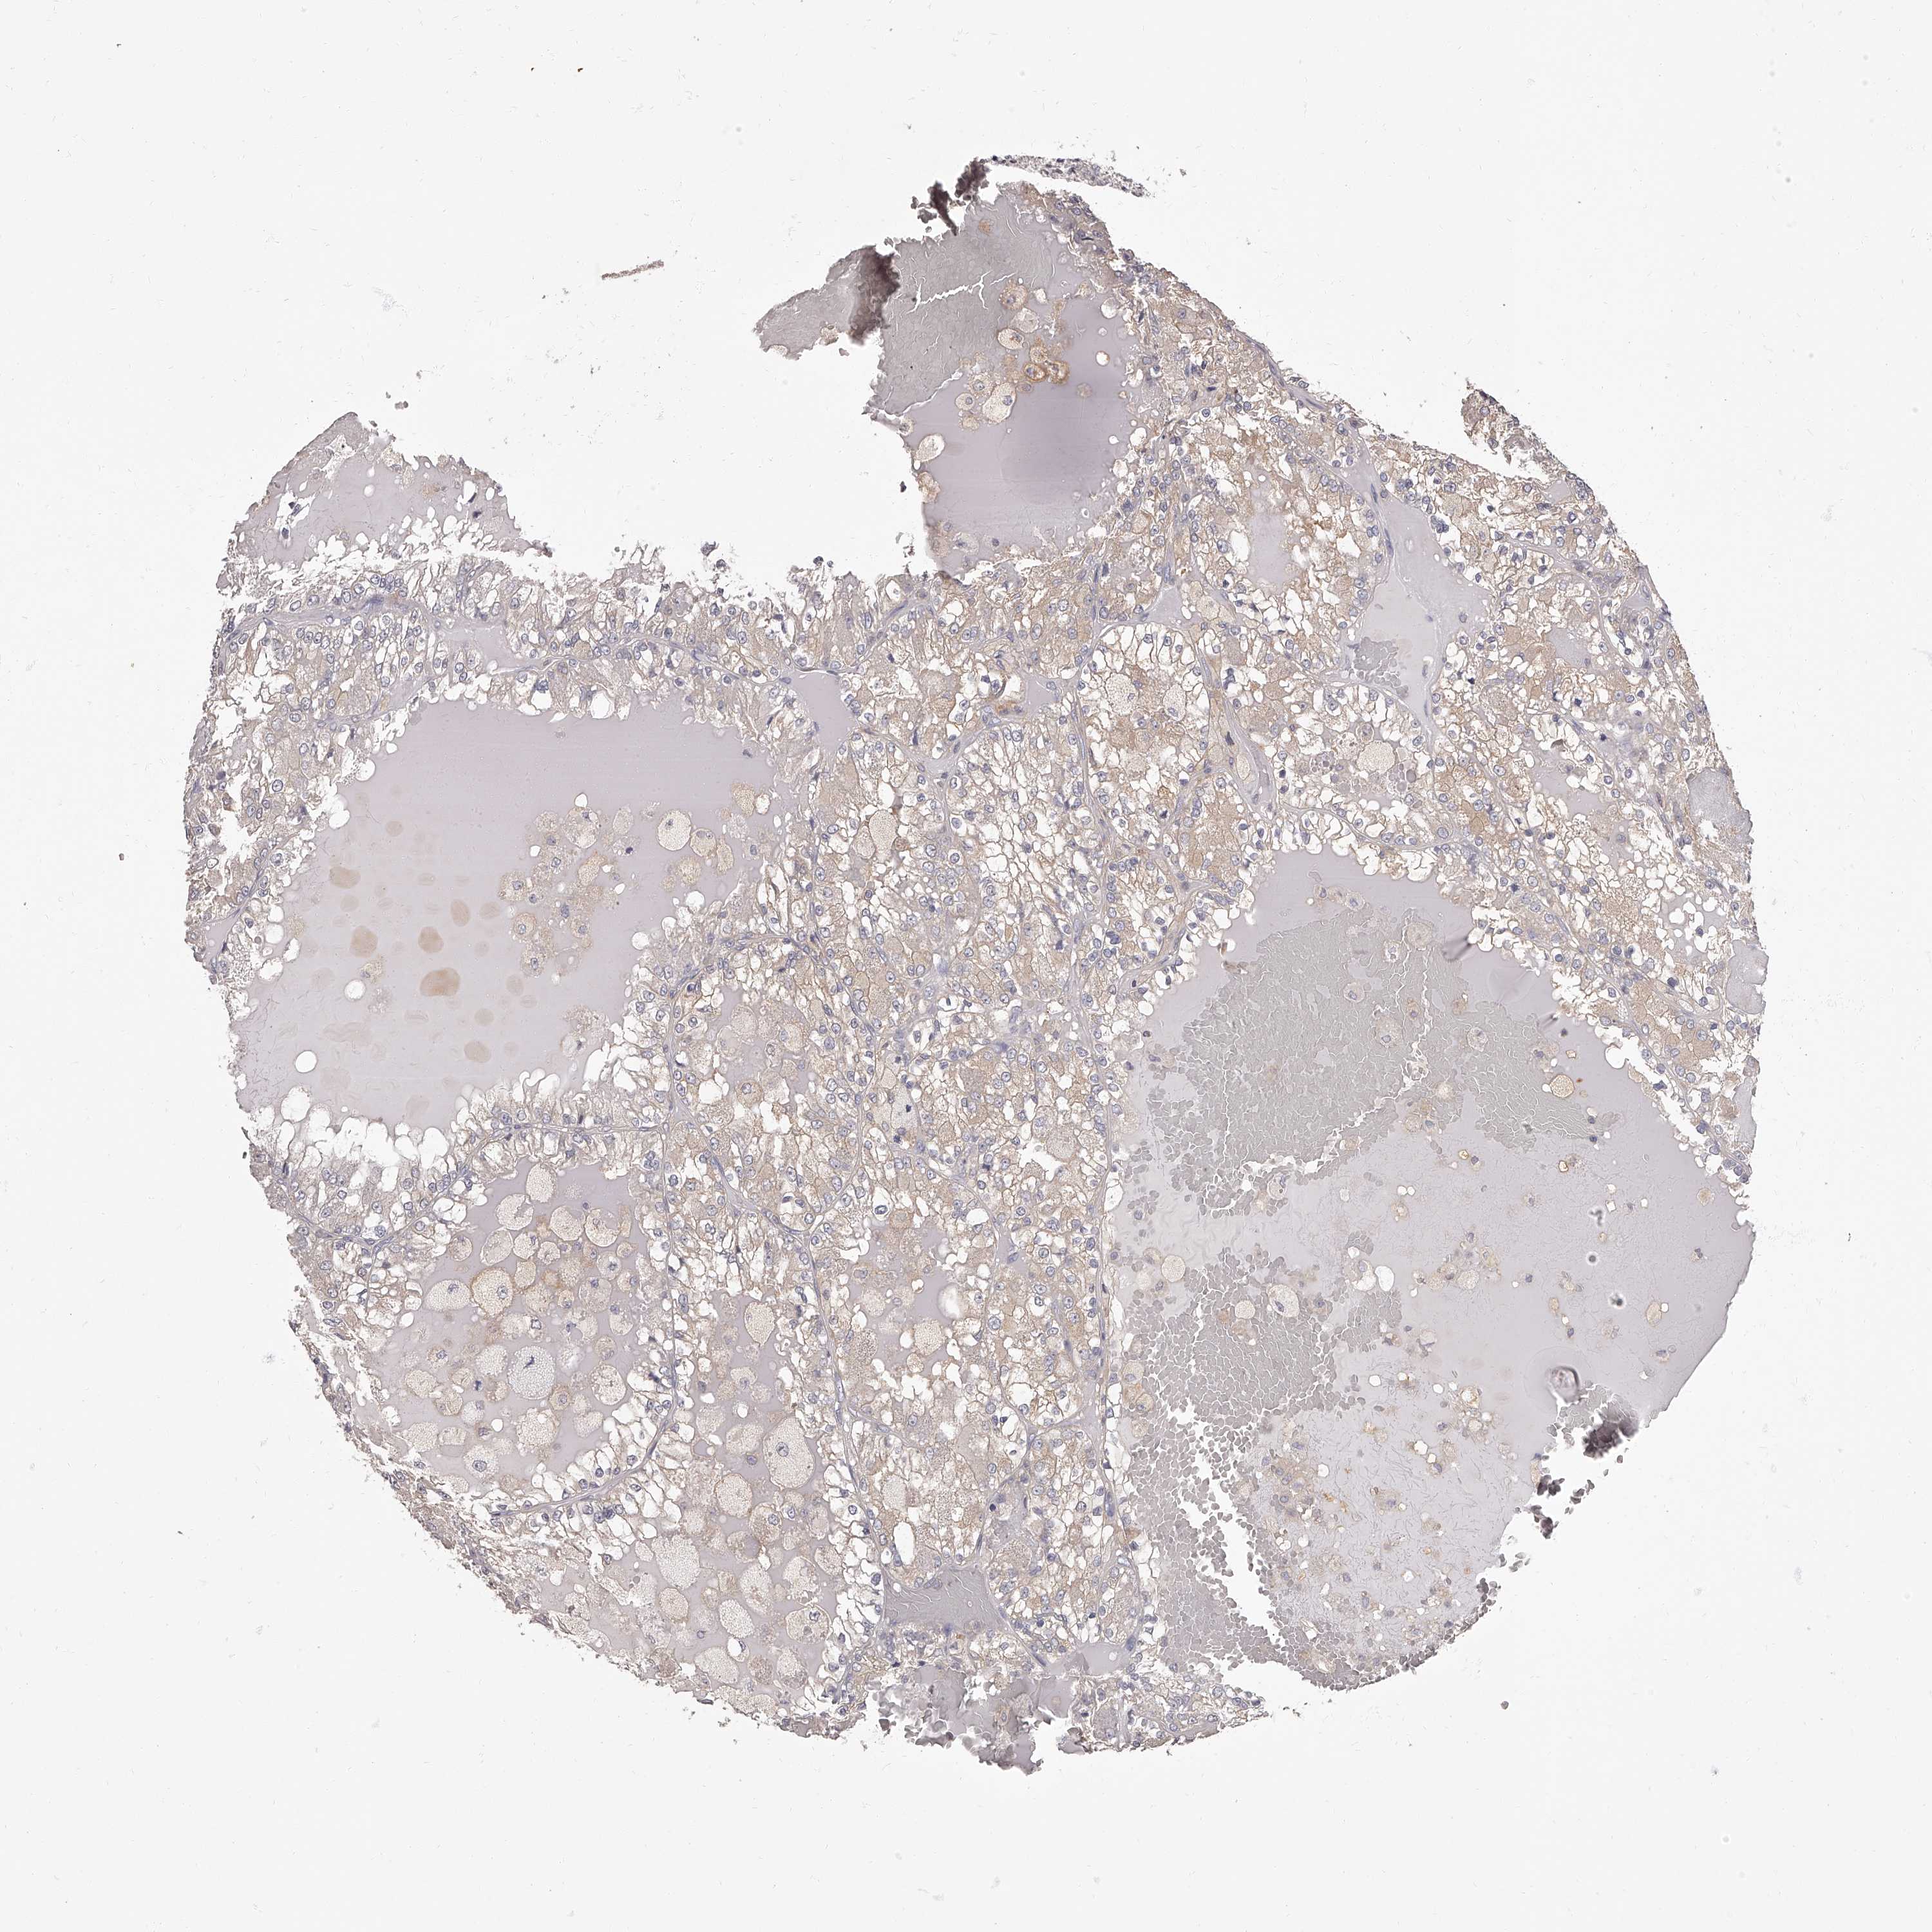

CANCER RENAL CANCER Show tissue menu

KICH TCGA KIRC TCGA KIRC VALIDATION KIRP TCGA PROTEIN RCC CPTAC PROTEIN EXPRESSION